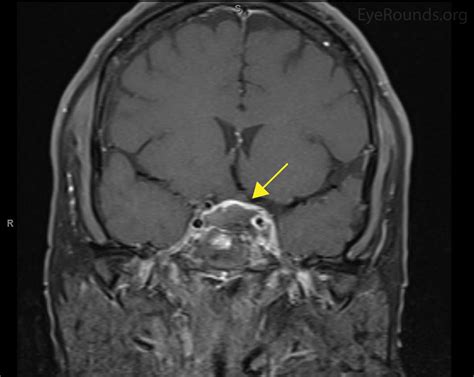

Diagnosing Cavernous Sinus Syndrome requires a high index of clinical suspicion and advanced imaging techniques. Physicians often utilize a combination of clinical evaluation and diagnostic testing to pinpoint the underlying etiology. Because the syndrome can be caused by various factors—from infections like sinusitis to malignant tumors or cavernous sinus thrombosis—the approach must be comprehensive.

MRI (Magnetic Resonance Imaging) Provides detailed views of soft tissues, identifying tumors, aneurysms, or inflammation.

• Inflammatory/Autoimmune: Tolosa-Hunt syndrome, a rare granulomatous inflammation, is a classic cause of painful ophthalmoplegia originating in the cavernous sinus.

Treatment is strictly dependent on the underlying cause. If the syndrome is caused by an infection, high-dose intravenous antibiotics are the primary course of action. If the culprit is a tumor, treatment may involve surgical decompression, radiation therapy, or chemotherapy depending on the histological nature of the mass. In cases of vascular issues, such as a fistula, endovascular interventions like coil embolization are frequently used to restore normal blood flow dynamics and reduce pressure.